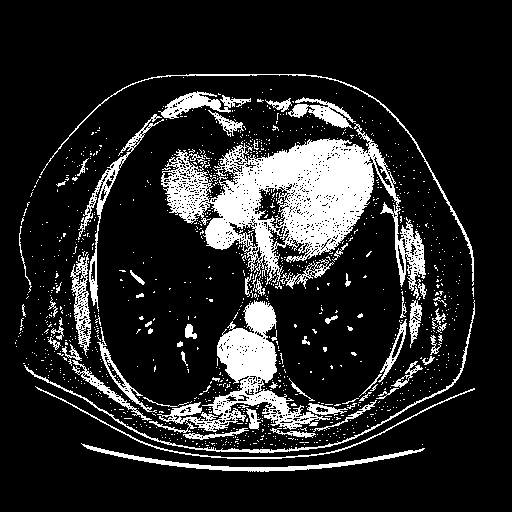

Original NATIVE CT scan (input)

Full window (WL 1023.5, WW 4095 β†’ Low βˆ’1024, High +3071)

Actual HU range: [-1024.0, 3071.0]